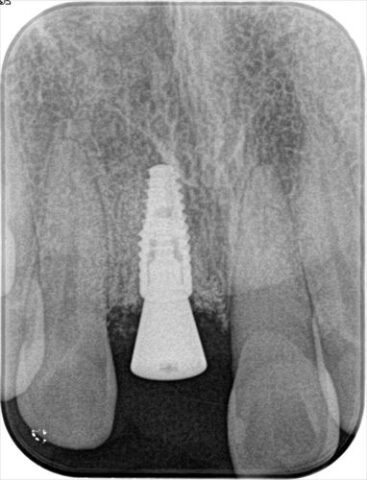

右上前歯部分にインプラントを埋入しました。2019.05.08|右上1・右上中切歯

広島市の自由診療専門歯科 三好デンタルオフィス 代表 三好龍治 です。右上中切歯部分にインプラントの埋入計画を立てます。まずはオフィス内の歯科用CTで撮影し、インプラントのポジショニングのシミュレーションします。  上下の歯列模型を採得し...